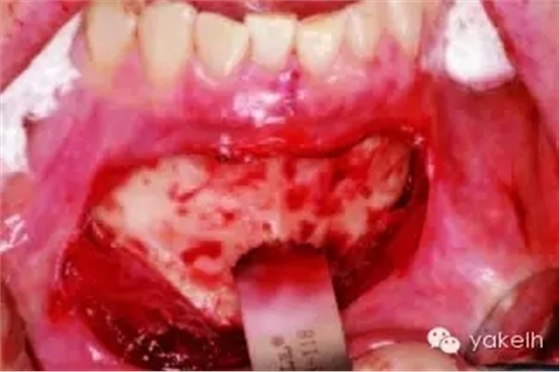

¤¤暴露頦部后,設(shè)計取骨的切口。取骨塊的大小由受區(qū)所需的骨量決定。骨切開處距離根尖以及頦孔最少應(yīng)有5mm。多數(shù)情況下,要保留下頜骨下緣以及舌側(cè)皮質(zhì)骨的完整性。唇側(cè)皮質(zhì)較厚,其內(nèi)側(cè)的松質(zhì)骨通常較致密。可以使用渦輪手機碳合金裂鉆(557號或701號)或者來復(fù)鋸將骨切開(圖13.19)。切透皮質(zhì)骨達(dá)松質(zhì)骨后,用骨鑿將骨塊移除(圖13.20)。用單面鑿沿著骨切開線輕輕敲擊,除了下頜骨下緣,將骨塊從基底部折斷。在中線處時,也可將塊狀骨分割成矩形骨塊,分段獲取。分成兩個骨塊后更容易獲取,因為可以用骨鑿將第二塊骨塊從舌側(cè)撬起。另外,移除塊狀骨后,還可使用骨刮匙、鑿子、咬骨鉗、環(huán)形鉆獲取

一些松質(zhì)骨,但是松質(zhì)骨的量十分有限。在移除塊狀骨后,可以將止血材料如膠原或明膠海綿置于松質(zhì)骨表面。當(dāng)獲取較大的骨塊時,供區(qū)應(yīng)使用骨替代材料如羥基磷灰石,來維持唇側(cè)的外形(圖13.21)。較少或者顆粒狀的骨移植時,可使用環(huán)形鉆、骨收集器、骨挖器來獲取。把骨塊植入受區(qū)后,再將供區(qū)的傷口縫合,這可以縮短取骨與植骨之間的時間。分離前庭溝切口上方的黏膜,以減少水腫和下唇運動所產(chǎn)生的張力。用可吸收縫線分層縫合前庭溝切口(圖13.22)。深層組織使用4-0可吸收線縫合,表層黏膜使用4-0鈷腸線縫合。術(shù)后使用壓力繃帶包扎頦部,以減少水腫、血腫形成及切口裂開(圖13.23)。